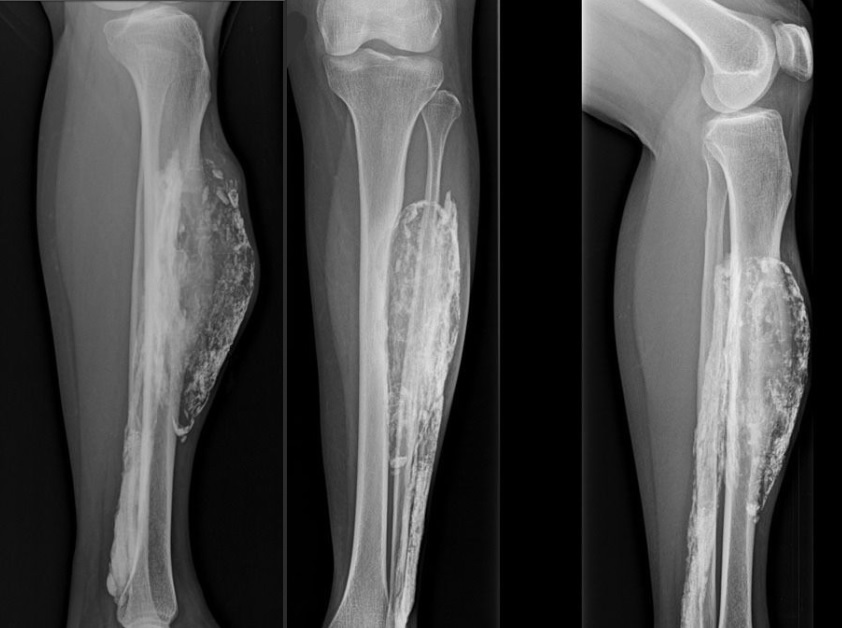

În urmă cu 10 ani, ea a observat la un picior o formaţiune ciudată. La radiografie, aceasta apărea ca o cavitate înconjurată de o membrană calcifiată asemeni unei coji de ou.

Masa calcifiată începe să se dezvolte atunci când ţesutul moare după o lovitură puternică sau în urmă întreruperii fluxului de sânge la picior. Formaţiunea este dură la atingere, se observă la radiografie, care nu este dureroasă.